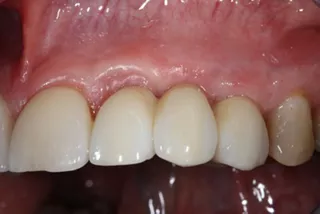

16a-b. Final situation after inserting bridges to 15 Ncm, cementing the crown to tooth 15, and gluing the veneers to teeth 11 and 21.

16c. 4 years post implant placement.

18. Situation 4 years post implant placement.